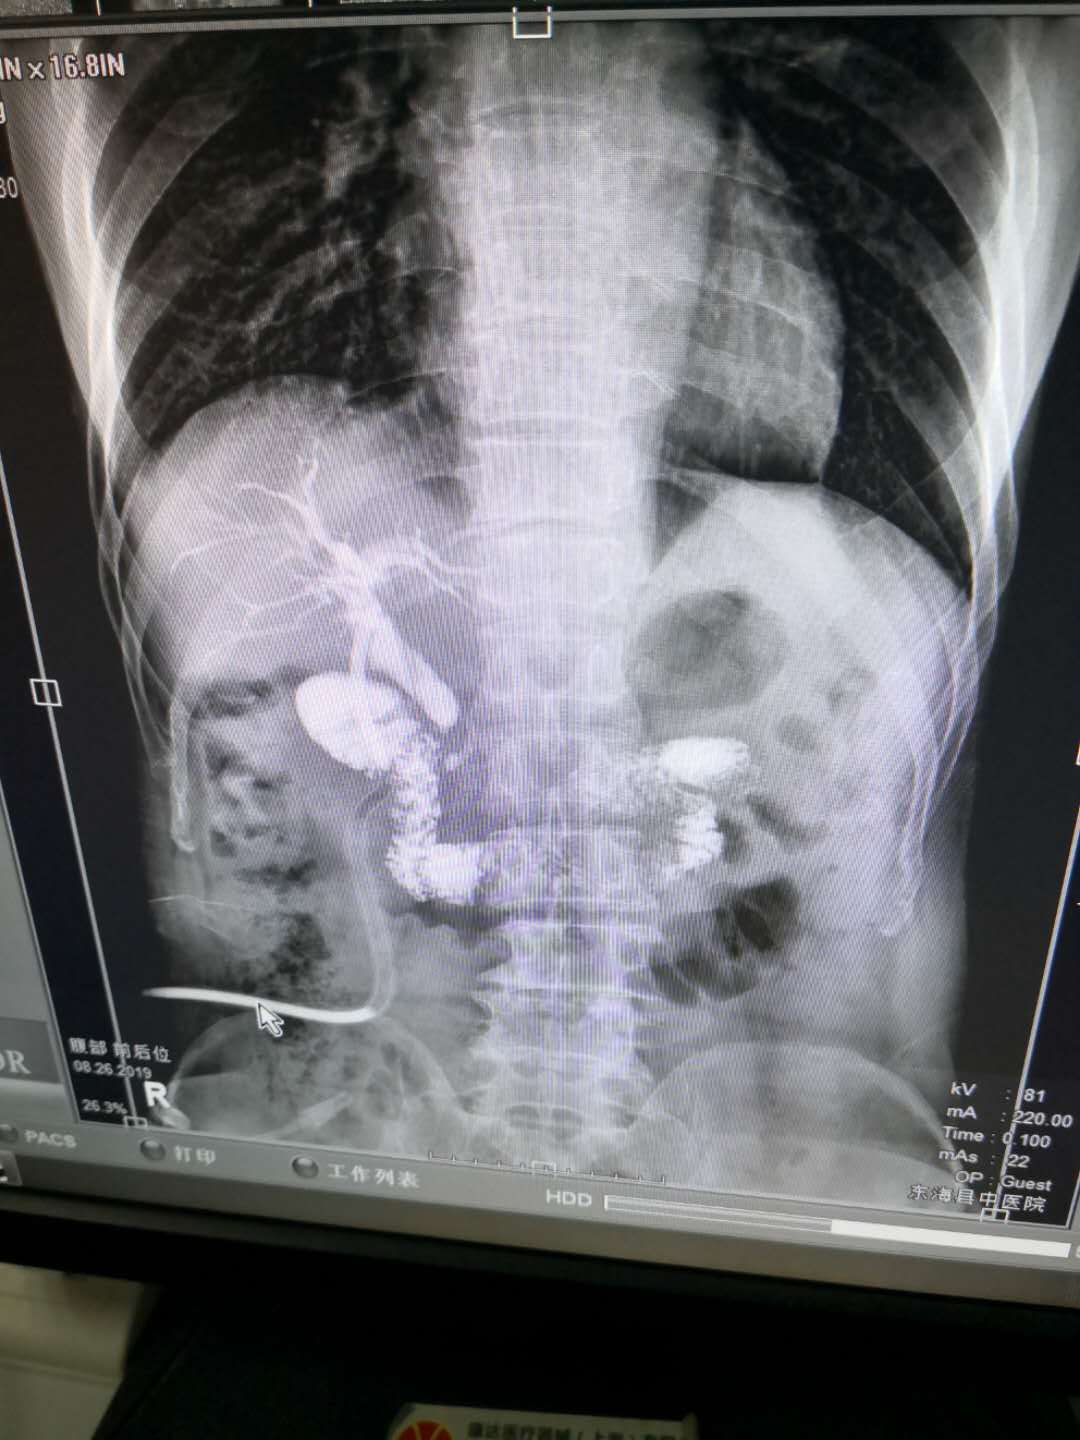

这种手术后一般需要放置两个管子,一个管子就是上图中间一张的T管,主要作用就是:1,支撑胆总管,防止切口的地方疤痕愈合形成狭窄。2,引流胆汁,防止压力过高导致胆漏。3,术后复查如仍有结石,可通过管道取石。第二根管子是放置在胆总管旁的,此管子主要作用是如发生胆漏,胆汁可及时的通过此管子引流出来,避免因胆漏而造成的二次手术可能。

第一根,也就是T管,一般在术后4-6周,做个胆道造影检查,没发现结石就可以拔除了,如发现结石,可通过此管道用胆道镜取石。